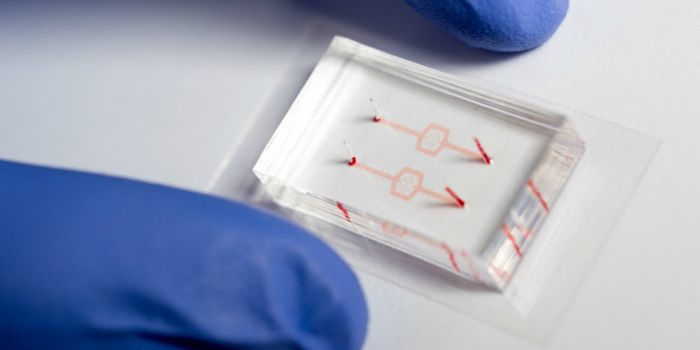

MAY 01, 2018CancerResearchers have developed a microfluidic device that can detect circulating plasma cells in whole blood; therefore, neg ...